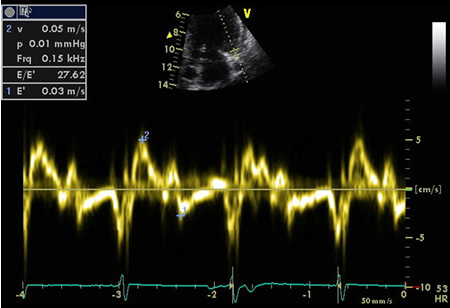

Doppler tecidual do ventrículo esquerdo (VE) basal exibindo E/E' elevado

Do acervo de Dr Jessica Webb; usado com permissão